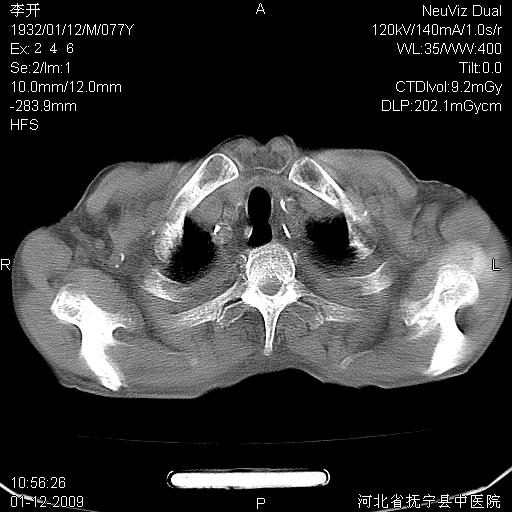

以下是引用黑白光影在2009-1-19 16:49:00的发言:[br]心衰肺水肿;心包、胸腔积液;冠脉钙化;肺部感染。